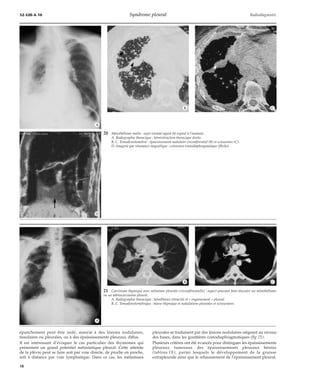

11 Atélectasie ronde ou,

mieux, « collapsus par enroule-ment

».

A. Schéma explicatif : phy-siopathologie

de l’épanche-ment

et sa « décrue » avec

réexpansion pulmonaire

imparfaite.

B, C, D. Même sujet à

1 mois d’intervalle.

*D

*A

ATÉLECTASIE RONDE OU COLLAPSUS

PAR ENROULEMENT [9, 13, 14, 15, 30, 31, 36, 38, 49]

L’enroulement de la plèvre viscérale qui emprisonne du parenchyme

pulmonaire détermine une opacité arrondie ou ovalaire, d’un

diamètre compris entre 2,5 et 6 cm, de topographie volontiers

postéro-inférieure ou latérobasale, mais au contact d’un

épaississement pleural constant. Le mécanisme de l’enroulement est

en effet lié à la phase de retrait d’un épanchement pleural (fig 11).

Cette opacité qui peut contenir un bronchogramme, voire des

calcifications, attire l’arborisation vasculaire selon un trajet

arciforme, réalisant ainsi une image en « queue de comète »

évocatrice. Le lobe qui la contient a perdu du volume (collapsus

11

12 Collapsus par enroulement (A ; flèche), épaississement pleural (A, B ; têtes de flèches) et « pieds de corneille »

(C ; flèches) : pleurésies bénignes répétitives chez des exposés à l’amiante.

partiel). L’étiologie la plus fréquente est représentée par l’exposition

à l’amiante et à sa maladie pleurale répétitive. La TDM est souvent

suffisamment démonstrative pour éliminer une néoplasie, si

fréquente sur ce terrain. La TDM précise les bandes linéaires

opaques, translobulaires, parenchymateuses, à implantation

pleurale, que l’on peut considérer comme des équivalents mineurs

de collapsus par enroulement, qui peuvent être nommées « pieds de

corneille » ou crow-feet [12, 13] (fig 12).